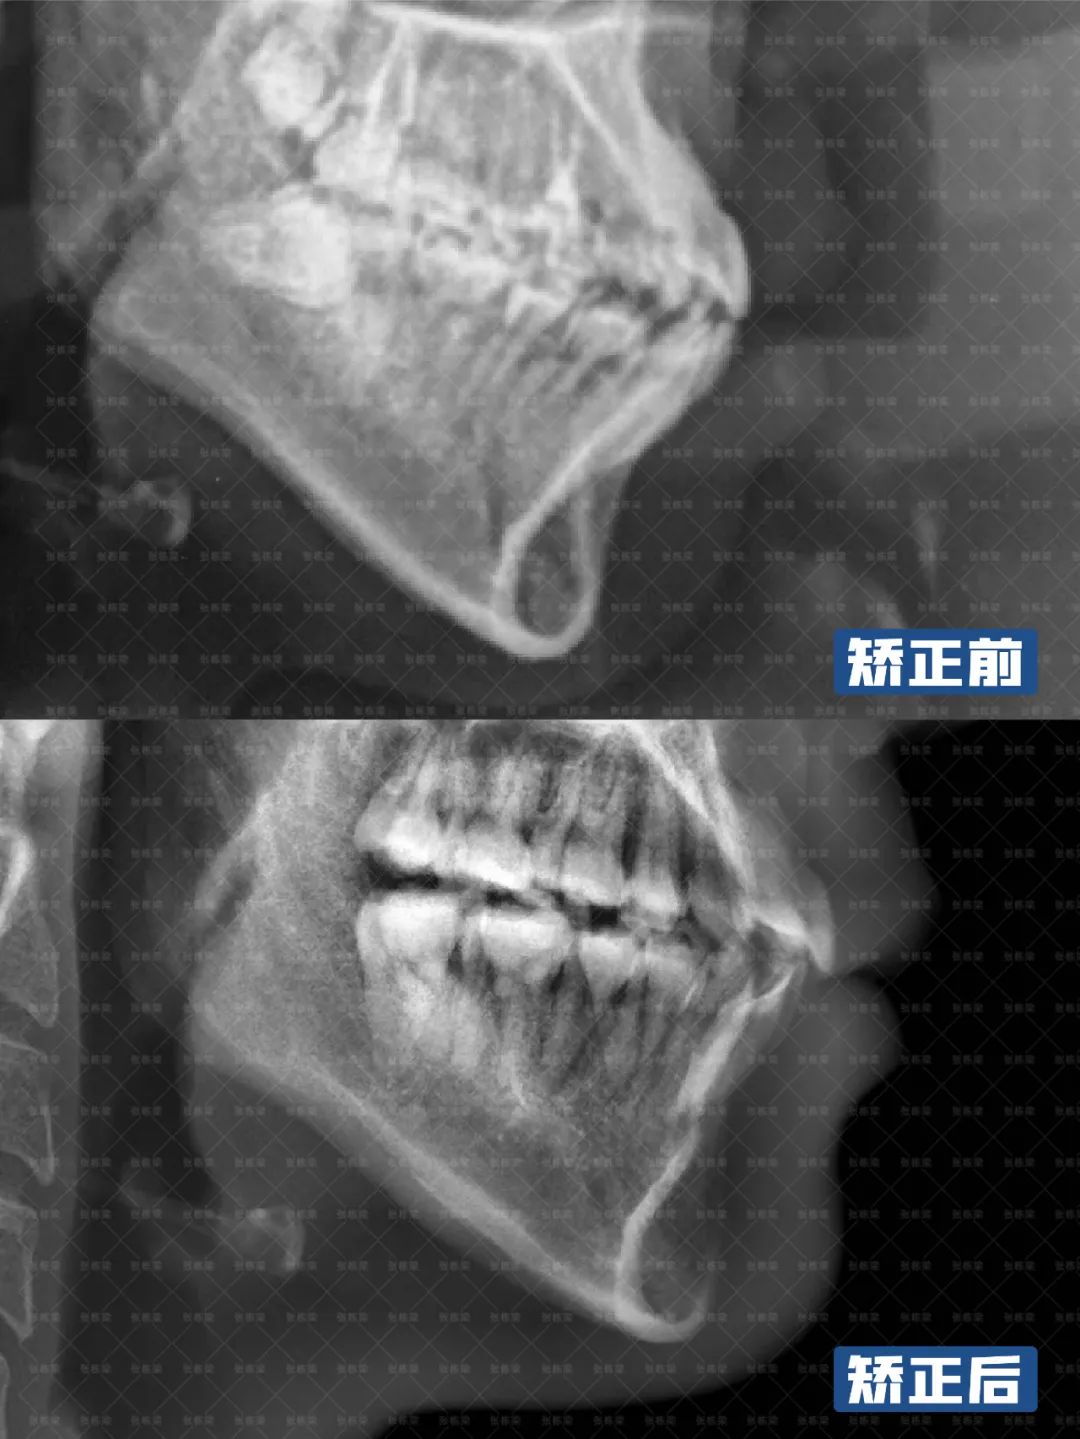

女士想要彻底改善嘴凸和牙齿不齐问题,牙齿矫正主要目标是内收上下颌,改善嘴突,前伸颏部,调整牙齿咬合,达到正常覆合覆盖,根据女士的要求,制定拔牙矫正的方案。

整个牙齿矫正过程,女士配合良好,可以看到上牙转矩角度正常,下前牙直立排齐,嘴凸内收、下巴出来之后,面下三分之一的软组织改善也比较理想。